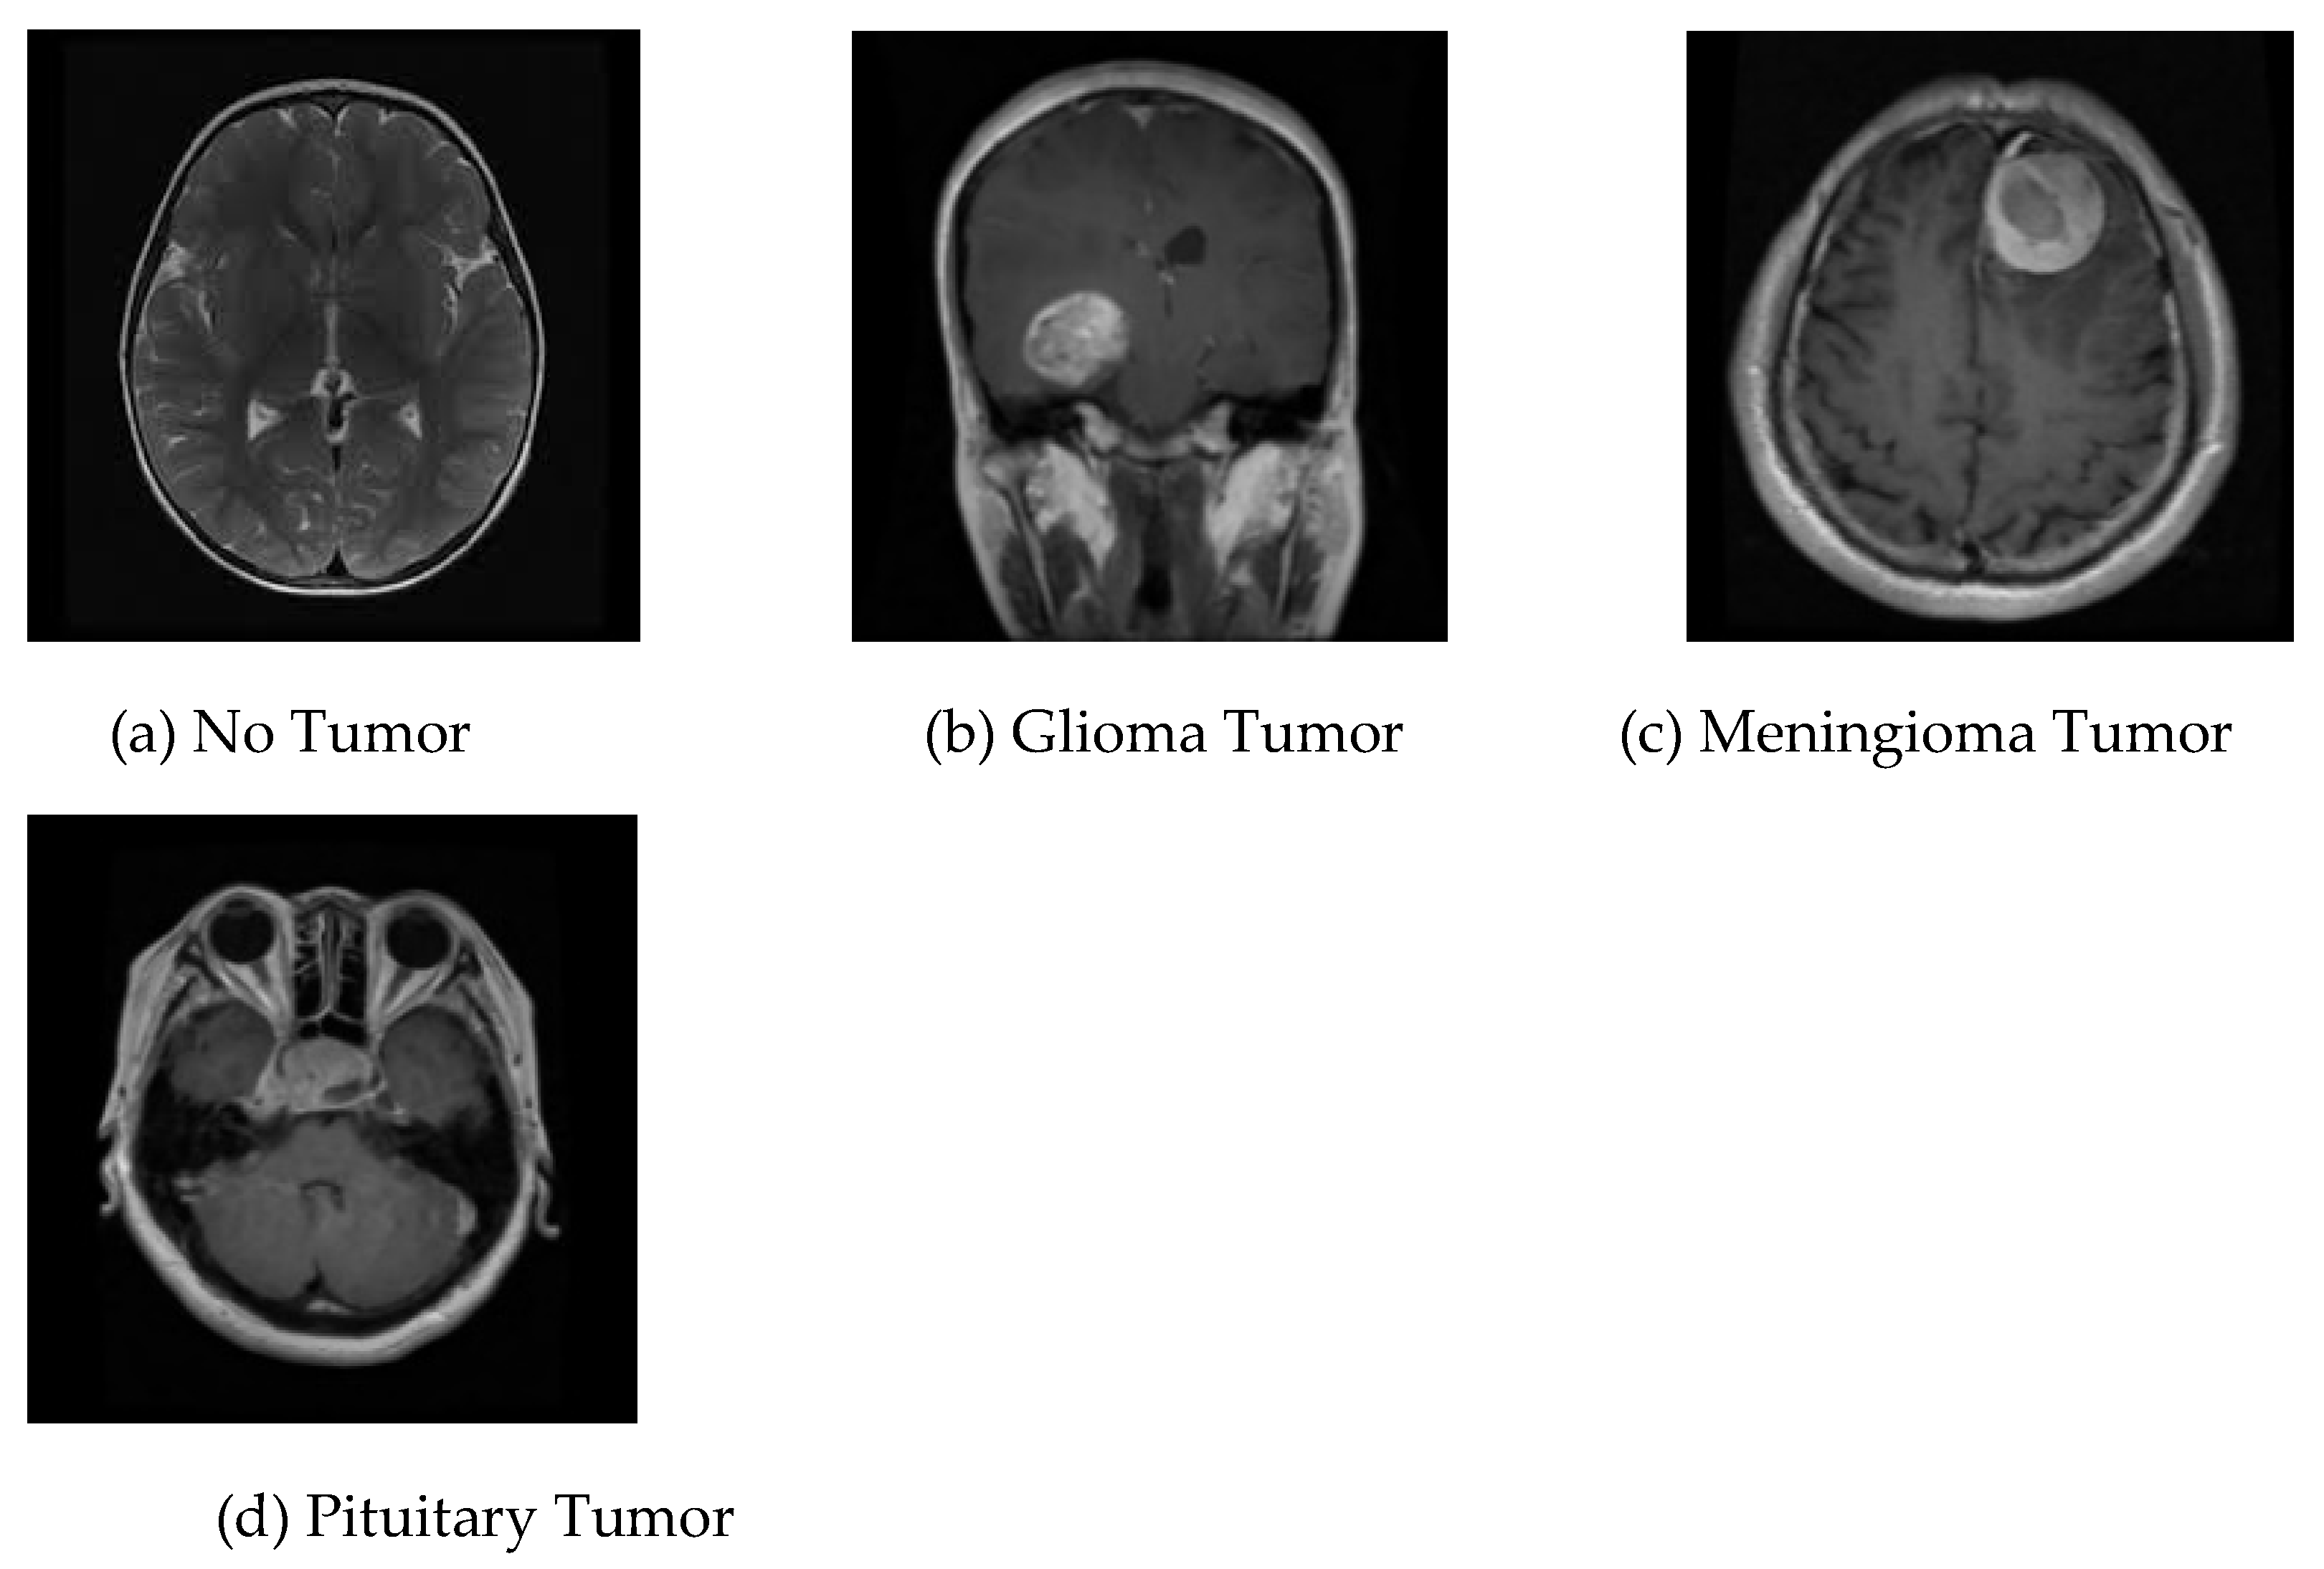

7]. Two MRI pictures of two distinct brains are shown in

Figure 1.

Dataset-Ⅰ: Through the Kaggle platform, the initial accessible dataset of binary-class MRI scans of the brain has been obtained for simplicity and this dataset is widely used. This data is known as dataset-I in this study [

8]. This set of 253 brain MRI images includes 98 samples with tumors and 155 samples without tumors.

Dataset-Ⅱ: The Figshare dataset containing 233 patients' brain MRI images is employed in this research [

13]. These brain MRI images are obtained at Nanfang Hospital and General Hospital, two Chinese medical centers. This dataset, designated dataset-II, comprises 3064 brain MRI scans, including 1426 glioma tumors, 708 meningioma tumors, and 930 pituitary tumors.

Dataset-Ⅲ: The additional dataset utilized in this study can also be obtained via the Kaggle website [

14]; it contains brain MRI images of glioma tumor, meningioma tumor, no tumor, and pituitary tumor, numbered 826, 822, 395, and 827, in that order. This collection of data is identified as dataset-Ⅲ in the current research. The four different kinds of brain MRI images that are present in dataset-Ⅲ are shown in

Figure 3.